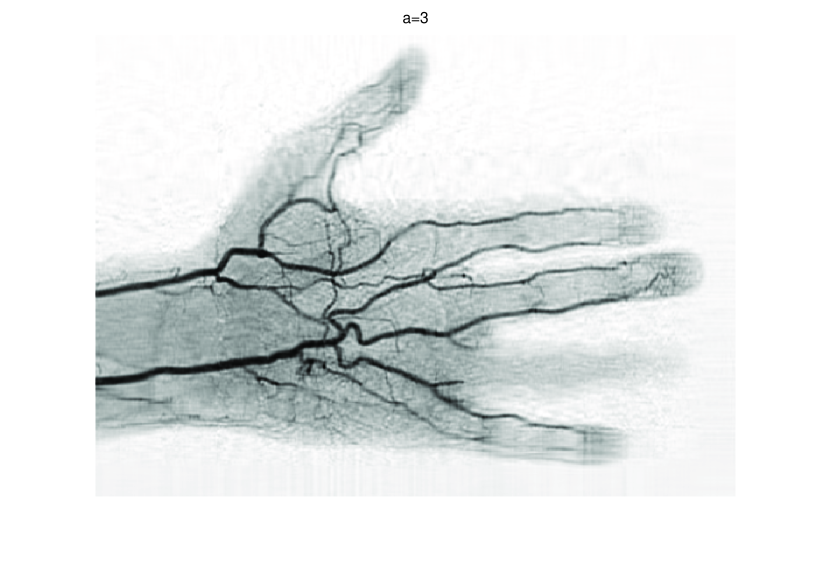

In this subsection, we demonstrate performances of ISVTA on image inpainting problems. The ISVTA is tested on some medical grace images (255×192255192255\times 192 Brain angiography image (BAI), 395×549395549395\times 549 Hand angiography image (HAI) and 419×400419400419\times 400 Intracranial venous image (IVI)). We use the SVD to obtain their approximated low-rank images with rank r=30,40,30𝑟304030r=30,40,30, respectively. Numerical results of ISVTA for theses low-rank image inpainting problems are reported in Table 5, 6, 7, 8.

Refer to caption

Figure 4: Original 395×549395549395\times 549 HAI and its approximation with rank 40.

Table 5, 6 show that ISVTA performs powerful in finding a low-rank matrix on image inpainting problems. Indeed, we could get an exact low-rank image by the ISVTA by choosing proper a𝑎a. Moreover, it is necessary to point out that our method does not work well for all a>0𝑎0a>0, and we can find that a=100𝑎100a=100 is not a good strategy for the low-rank IVI either SR=0.40SR0.40\mathrm{SR}=0.40 or SR=0.50SR0.50\mathrm{SR}=0.50. The numerical results of ISVT, SVTA and SVPA compared in Table 5, 6, 7, 8, 9, 10 under same circumstance show that the ISVT algorithm performs far more better than ISTA and SVPA on image inpainting problems for some proper a>0𝑎0a>0.

Figure 7: Comparisons of ISVTA, SVTA and SVPA for recovering the approximated low-rank HAI with SR=0.40.